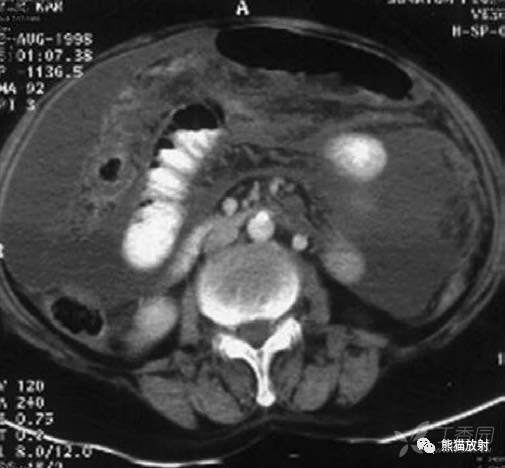

结核性腹膜炎。大网膜增厚,腹水,肠袢外移

结核性腹膜炎。大网膜增厚,腹水